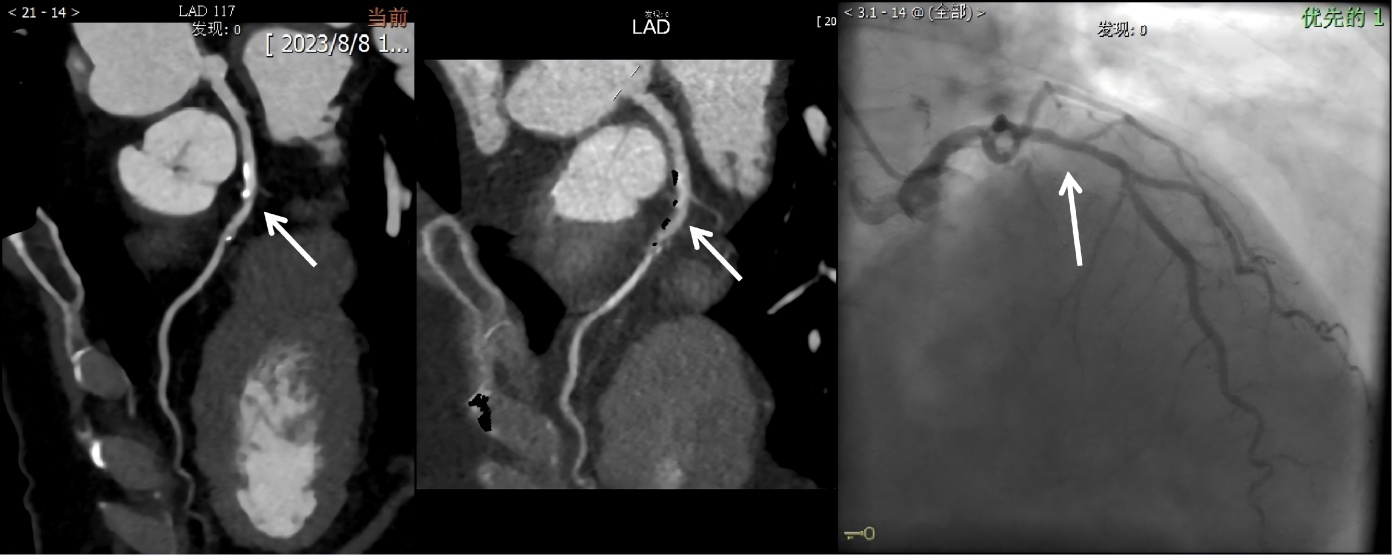

Figure 1. Images from standard post-processing CCTA, dual-energy subtraction CCTA, and coronary artery angiography

1. 标准后处理CCTA、双能量减影CCTA及冠状动脉造影图像

相关文献报道,标准重建CTA诊断为严重钙化斑块中,约有38.7%~50%的节段被判定为无诊断意义[10],通过减影技术,消除造影剂增强以外的高密度区域以及相关伪影,将会使评估管腔变得更容易[13]。本研究中证实,双能量减影组对于重度及闭塞病变的诊断准确率和特异度分别为82%、93.2%,其特异性显著优于标准组,结果显示标准重建存在较严重的假阳性问题,即容易将轻、中度的狭窄过度诊断为重度狭窄或闭塞,而这一情况通过双能量重建得到较好的解决。如图1所示,74岁的女性患者,在标准后处理CCTA显示LAD近段中度狭窄,双能量减影CCTA显示管腔轻微狭窄,与CAG结果一致。本研究结果中诊断一致性和相关性显示,双能量减影组均优于标准重建组,表明冠状动脉双能量减影技术在诊断管腔狭窄方面有较好的应用价值,有助于提高医师的诊断信心。